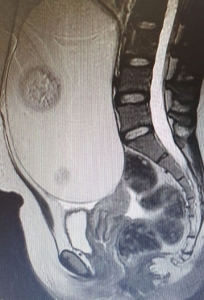

Pacienta, în vârstă de 21 de ani, a fost diagnosticată întâmplător. Pentru că acuza dureri abdominale nespecifice, femeia s-a prezentat la Spitalul Mioveni, secția Obstetrică-Ginecologie. În urma consultului, i s-a recomadat și un examen RMN, care a evidențiat tumora.

Intervenția a durat două ore și jumătate, fiind dificilă pentru că tumora ocupa aproape în întregime cavitatea abdominală. Evoluția postoperatorie a fost favorabilă, iar pacienta s-a externat la două zile după operație.